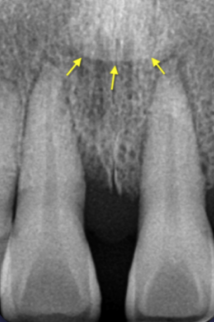

Incisive foramen

dark circle between upper central incisors